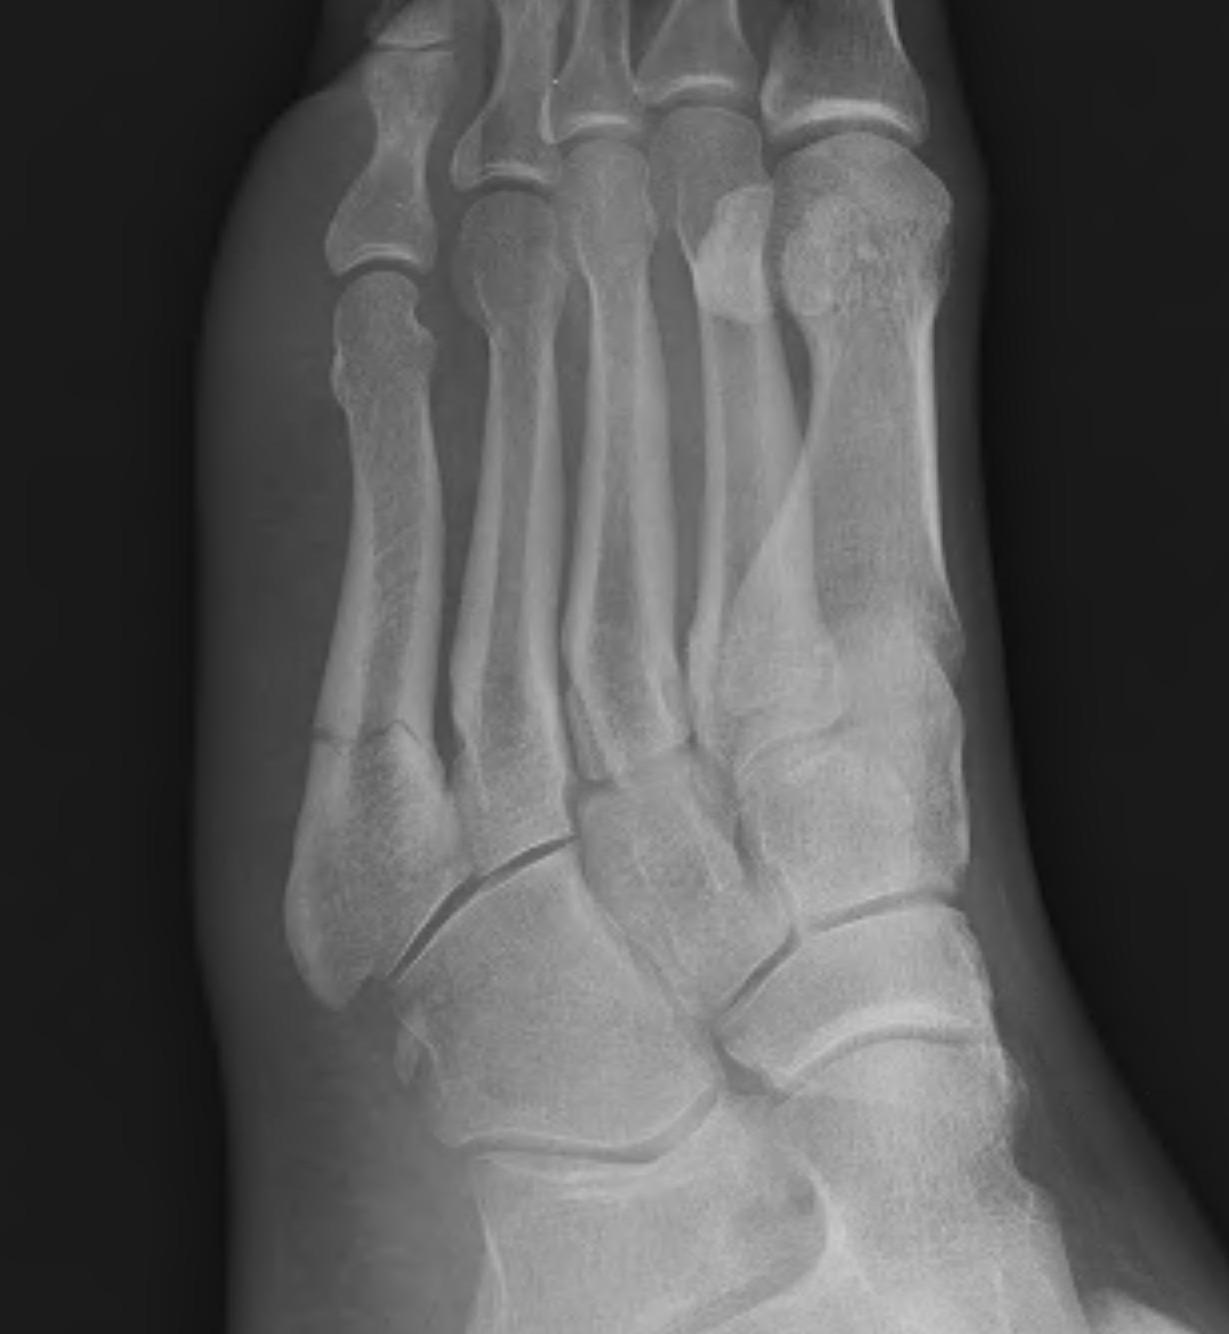

(a) The fifth metatarsal base avulsion fracture confirmed by Xray. (b Metatarsal Fracture Cast These long thin bones are located between the. You might need a special shoe, boot, or cast. a metatarsal bone fracture is a complete or incomplete break in one of the five metatarsal bones in each foot. Most metatarsal fractures result from an acute injury, although chronic stress fractures and. Your doctor will tell you how much. This may. Metatarsal Fracture Cast.

Fractures of the Fifth Metatarsal Base UW Emergency Radiology Metatarsal Fracture Cast These long thin bones are located between the. a metatarsal bone fracture is a complete or incomplete break in one of the five metatarsal bones in each foot. metatarsal fractures are among the most common injuries of the foot that may occur due to trauma or repetitive. a metatarsal fracture occurs when one of the long bones. Metatarsal Fracture Cast.